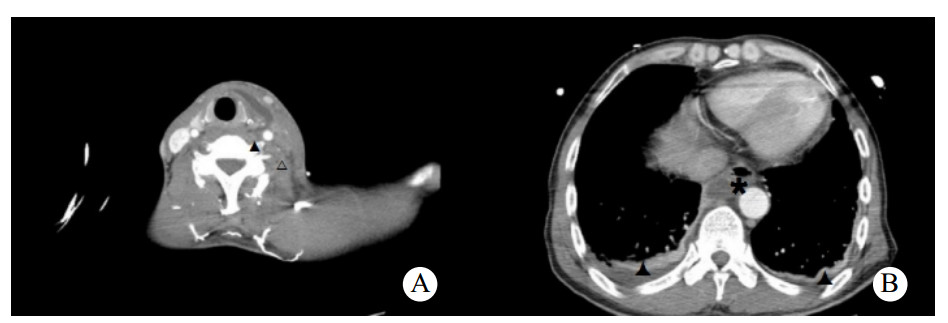

患者男,50岁,因“进行性左侧咽痛6 d”于2019年4月30日入院。患者6 d出现左侧牙痛、咽痛,伴发热(体温不详),未予治疗。3 d前咽痛加重,遂至当地医院就诊,CT提示左侧咽旁软组织肿胀伴喉腔变窄,超声提示左侧颌下腺炎,予以头孢米诺钠抗感染治疗后咽痛无好转,并出现呼吸困难及胸闷,左侧颈部肿痛。10 h前转入本院急诊就诊。否认糖尿病、高血压、吸烟、饮酒史。查体:双侧扁桃体无肿大充血,左侧咽侧壁肿胀,左侧颌下及颈部肿胀,压痛明显,局部皮肤红肿,皮温升高。血常规:白细胞计数7.2×109/L、中性粒细胞6.14×109/L、中性粒细胞百分比85.2%。C反应蛋白 > 270.0 mg/L。凝血谱:D-二聚体2960 μg/L、血浆纤维蛋白原10.98 g/L。颈胸部增强CT:左侧咽旁间隙、左侧颈部、中后纵膈脓肿形成,左侧颈内静脉血栓形成考虑,双侧胸腔积液。见图 1。拟诊为咽旁脓肿,纵膈脓肿,左侧颈内静脉血栓,胸腔积液。急诊行颈侧切开咽旁、颈部脓肿切排引流,纵膈胸膜切开排脓、胸腔脓肿清除、胸腔闭式引流。颈部留置引流管2根,食管后间隙留置胸管1根,右侧胸腔留置胸腔引流管1根。脓液送细菌培养和药敏检查。患者带气管插管入住ICU,予注射用亚胺培南西司他丁钠(泰能)0.5 g每6 h一次抗感染,那屈肝素钙注射液(速碧林)0.4 mL每12 h一次抗凝治疗,注射用甲泼尼龙琥珀酸钠(甲泼尼龙)40 mg每日3次抗炎,以及化痰、护胃、补液等对症支持治疗。术后第2天转入普通病房,细菌培养及药敏结果:咽峡炎链球菌,对当前使用抗生素敏感,未更改抗生素。术后2次血培养结果均为阴性。术后持续牙痛并有持续性低热,请口腔外科会诊,考虑牙源性感染,建议待感染控制后拔除病灶牙。术后白细胞总数逐渐增加,C反应蛋白及降钙素原逐渐下降。术后第9天,出现左侧颌下及颈部肿胀,压痛明显,局部皮肤红肿,皮温升高,急诊行颈部及胸部CT提示:咽旁、颈部、纵膈脓肿术后改变,左侧颈部软组织内及上纵隔积气。两肺背侧少许渗出,两侧少量胸腔积液伴部分肺组织膨胀不全,较前5月1日渗出有吸收,积液有增多,右侧叶间包裹性积液。考虑颈部引流不畅,急诊行颈侧切开颌下、咽旁、颈部脓肿切排引流,颈部重新放置2根引流管。术后白细胞总数开始下降。术后22 d出院,复查颈静脉超声(图 2A)提示左侧颈内静脉闭塞,出院后改用利伐沙班片20 mg口服每日3次,抗凝治疗3个月。术后4个月复查超声(图 2B),左侧颈内静脉部分再通。

| A:▲为颈部增强CT提示左侧咽旁间隙脓肿形成,△为左侧颈内颈内血栓形成;B:胸部增强CT提示纵隔脓肿,双侧胸腔积液 图 1 入院时的颈胸部增强CT |